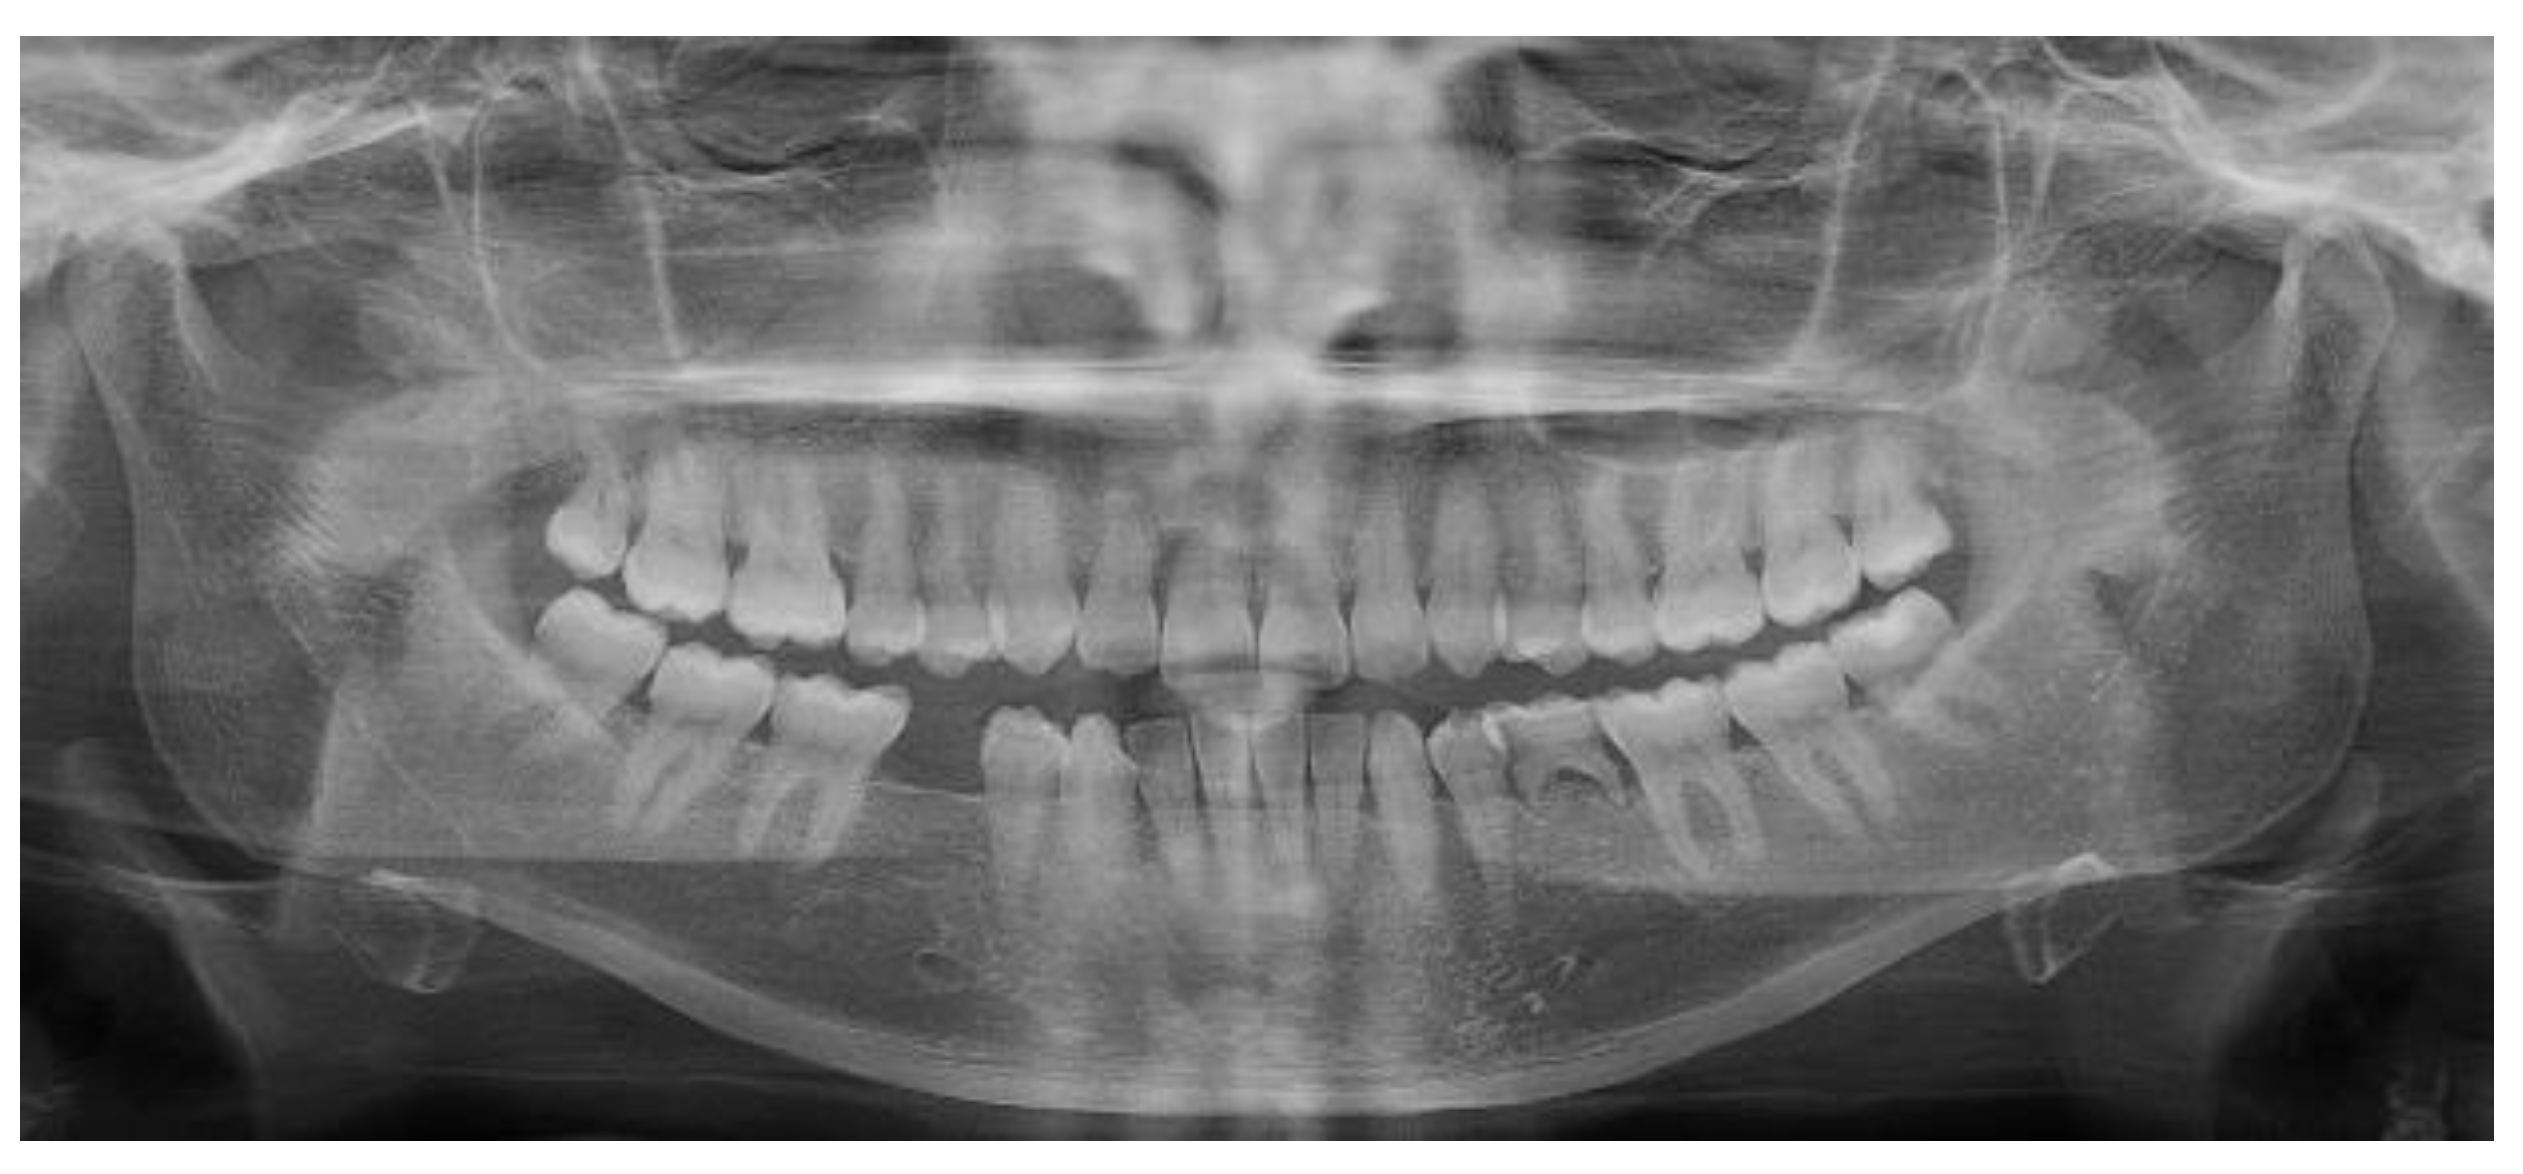

3.1. Clinical Results

3.2. Marginal Bone Level Outcomes